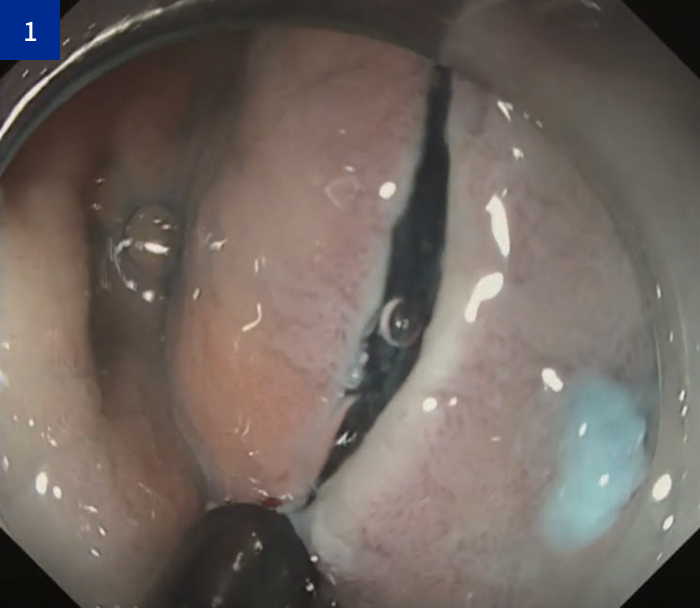

Step 1:全周切開 ~ トリミング

• ・粘膜切開では、ITknife 2を「引く」のではなく「押し付けながら引く」ことが重要である。

・また、ナイフの「引きシロ」を十分に確保することで、効率的にトリミングを進めることができる。

• 全周切開 ~トリミング